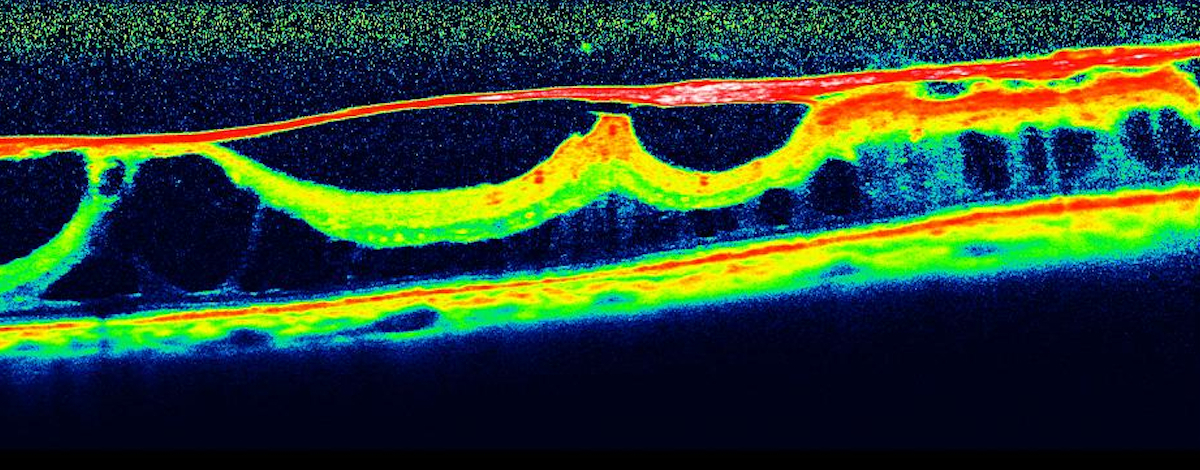

OCT

L’OCT, senza l’utilizzo di mezzi di contrasto, permette, attraverso l’uso di una sonda laser ad infrarossi, di ricostruire l’anatomia della retina nella regione maculare.

In caso di membrana epiretinica aiuta nella diagnosi e fornisce una quantificazione del problema.